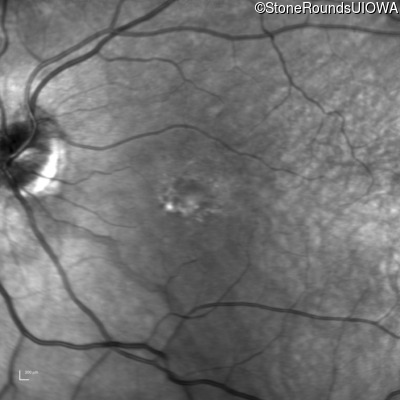

This 30 year old man has had reduced acuity and abnormal color vision OU since early childhood.

The clinical features supporting the diagnosis of blue cone monochromacy in this patient include: stable reduced acuity, photophobia and very poor color vision since early childhood, a normal fundus appearance, normally sighted parents and three similarly affected male relatives on the maternal side of his family.